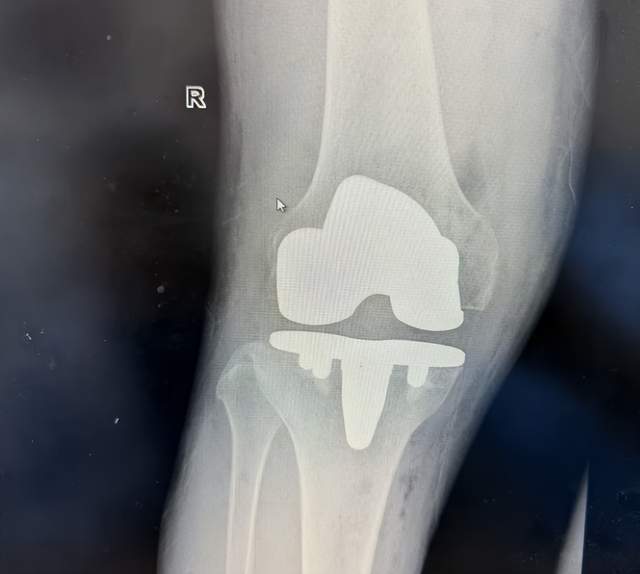

术后次日,张大叔在助行器辅助下站立活动时激动地表示:“走路不疼的感觉真好!”骨科康复治疗师陈志梦介绍,生物型置换因无需等待骨水泥固化,术后康复速度提升30%左右,这对老年患者尤为关键。

康复密码:因无需骨水泥凝固等待期,患者通常术后6小时即可开始踝泵运动,48小时内下地,住院时间缩短至3-5天。

术后影像